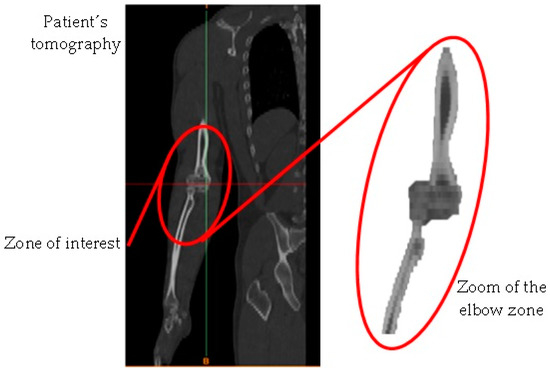

- Obtaining of the computerized axial tomography (upper limb).

- Development of images in DICOM format.

- Image importation into the Materialise Mimics® computer program.

- Delimitation of the area of interest for the development of the biomodel (elbow).